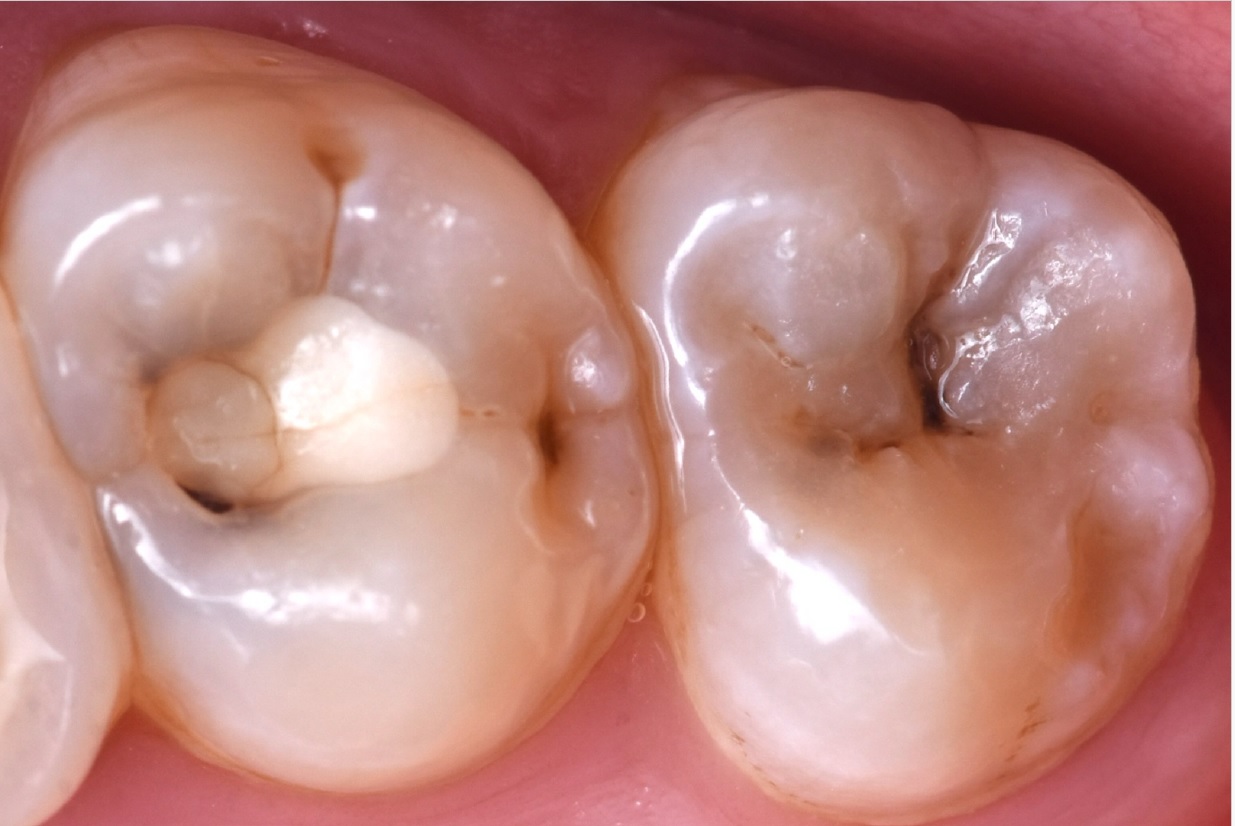

Εικ. 1: Ασθενής 21 ετών προσήλθε στην κλινική με ευαισθησία στο κρύο στο άνω δεξιό τεταρτημόριο. Η ενδοστοματική κλινική εξέταση αποκάλυψε μια παλιά, αποκατάσταση σύνθετης ρητίνης στον δεύτερο άνω γομφίο με ρωγμές και τερηδόνα στον τρίτο γομφίο. Η ακτινογραφία επιβεβαίωσε μια βαθιά τερηδονική αλλοίωση στον τρίτο γομφίο και την παρουσία μιας κατεστραμμένης αποκατάστασης σύνθετης ρητίνης στον δεύτερο γομφίο.